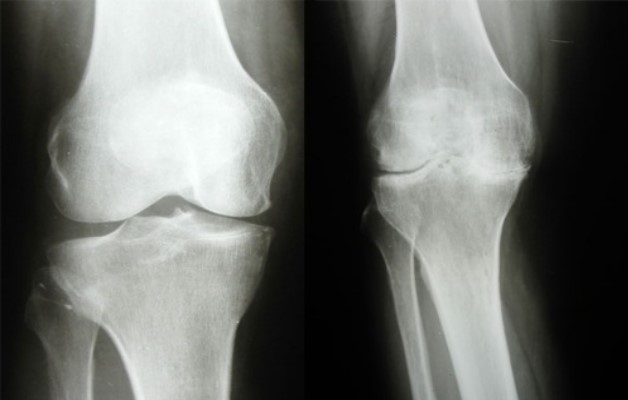

Для уточнения диагноза проводят инструментальные исследования и делают анализы:

Полезно знать. Инструментальные исследования включают рентген, который позволяет выявить артрозные изменения в суставном сочленении, компьютерную томографию и МРТ.